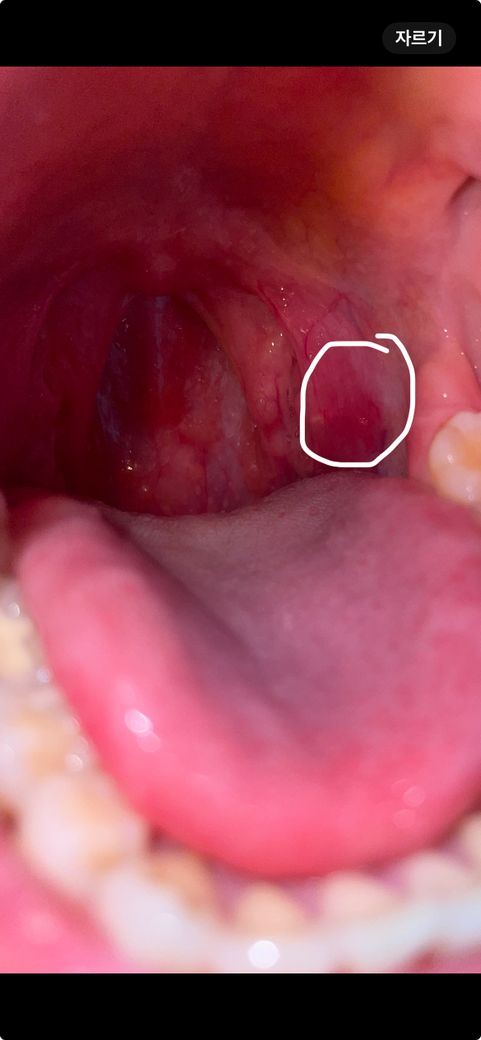

입안 뾰루지랑 편도쪽 부음 무슨증상인가요?

이빈후과에선 신경쓰지말라고 하는데 아무래도 계신경이 쓰이네요 신경안써도 될까요?? 뾰루지랑 편도쪽 비대칭 이상없는지 궁금해요

네 사진상으로 봤을때 이상 소견은 관찰되지 않습니다. 현재 말씀하신 부분이 증상을 따로 일으키지 않기 때문에 지켜보시기 바랍니다.